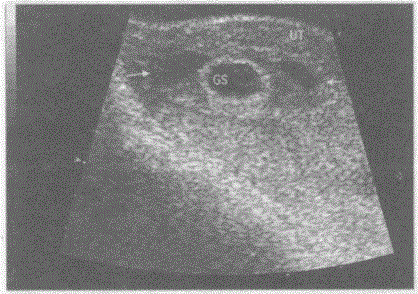

问题 临床资料:女,28岁,自述停经52天,阴道少量出血。 超声综合描述:子宫形态饱满,宫腔内见胎囊,内未见胎芽及胎心搏动,可见卵黄囊回声,胎囊旁另见形态不规则无回声区。 超声提示:

选项 A.宫腔积液 B.宫内早孕胚胎停止发育 C.宫内早孕(三胎) D.宫内早孕先兆流产胎膜后出血

答案 D